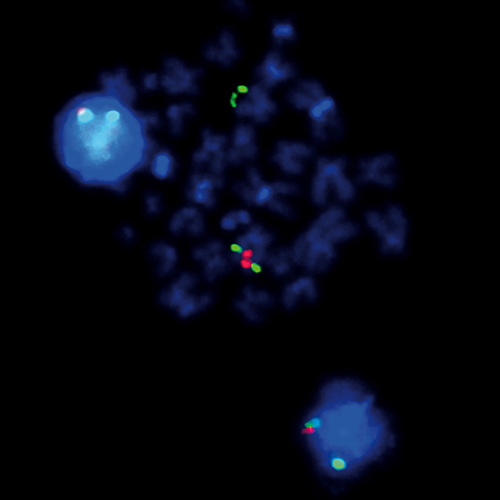

5q- (5q31; 5q33) probe hybridized to patient material showing a 5q33 deletion (1R2G).

IVD 5q Dual-Color

The presence of del(5q), either as the sole karyotypic abnormality or as part of a more complex karyotype, has distinct clinical implications for myelodysplastic syndromes (MDS) and acute myeloid leukemia. Interstitial 5q deletions are the most frequent chromosomal abnormalities in MDS and are present in 10% to 15% of MDS patients. Two different critical regions are described, one at 5q31-q33 containing the CSF1R and RPS14 gene regions, characteristic for the '5q-' syndrome, and a more proximal located region at 5q13-q31 containing the CDC25C and EGR1 gene regions. The 5q- specific FISH probe is optimized to detect copy numbers at the CDC25C/EGR1 gene region at 5q31 and the CSF1R/RPS14 gene region at 5q33 simultaneously in a dual-color assay.